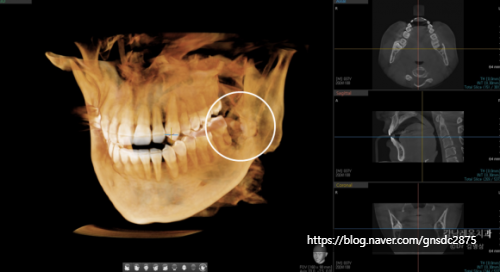

CT상으로도 남은 뿌리가

신경관과 매우 근접해 보여

거리를 정확하게 파악하여

조심스럽게 발치하기로 하였습니다.